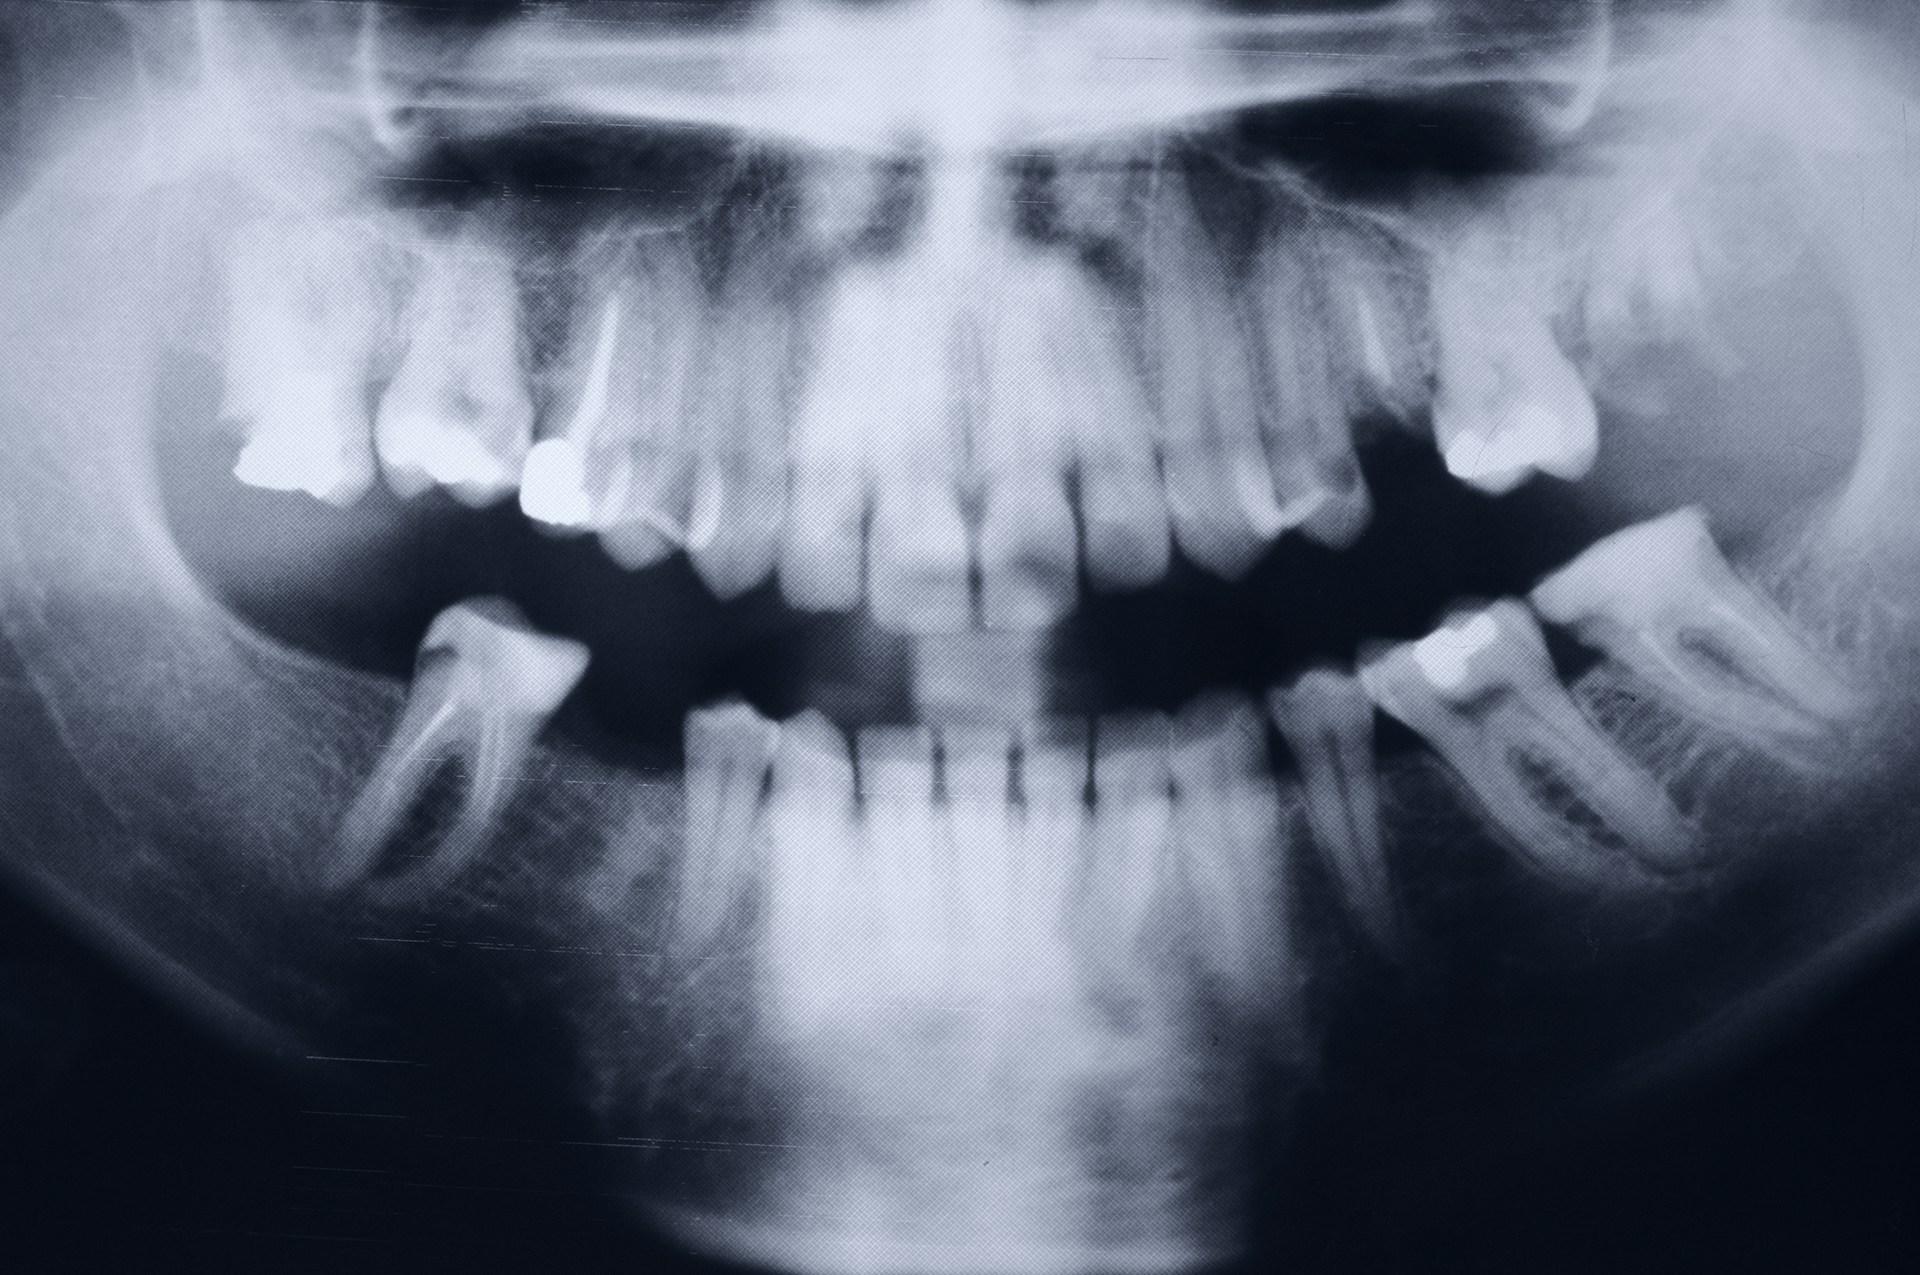

Ортопантомограмма (ОПТГ), или панорамный снимок зубов, представляет собой одноплоскостное изображение обеих челюстей. Для его получения пациента приглашают стать у аппарата, надевают защитный воротник и просят прикусить пластиковый держатель. Затем рентгеновский излучатель начинает вращение вокруг головы, которое длится около 15 секунд. Панорамный 2D-снимок помогает врачу:

- определить положение и состояние каждого зуба верхнего и нижнего рядов, увидеть очаги не только явного, но и скрытого кариеса;

- получить более достоверную информацию, чем та, которую дает прицельный снимок, о третьих молярах, или «восьмерках», называемых также зубами мудрости;